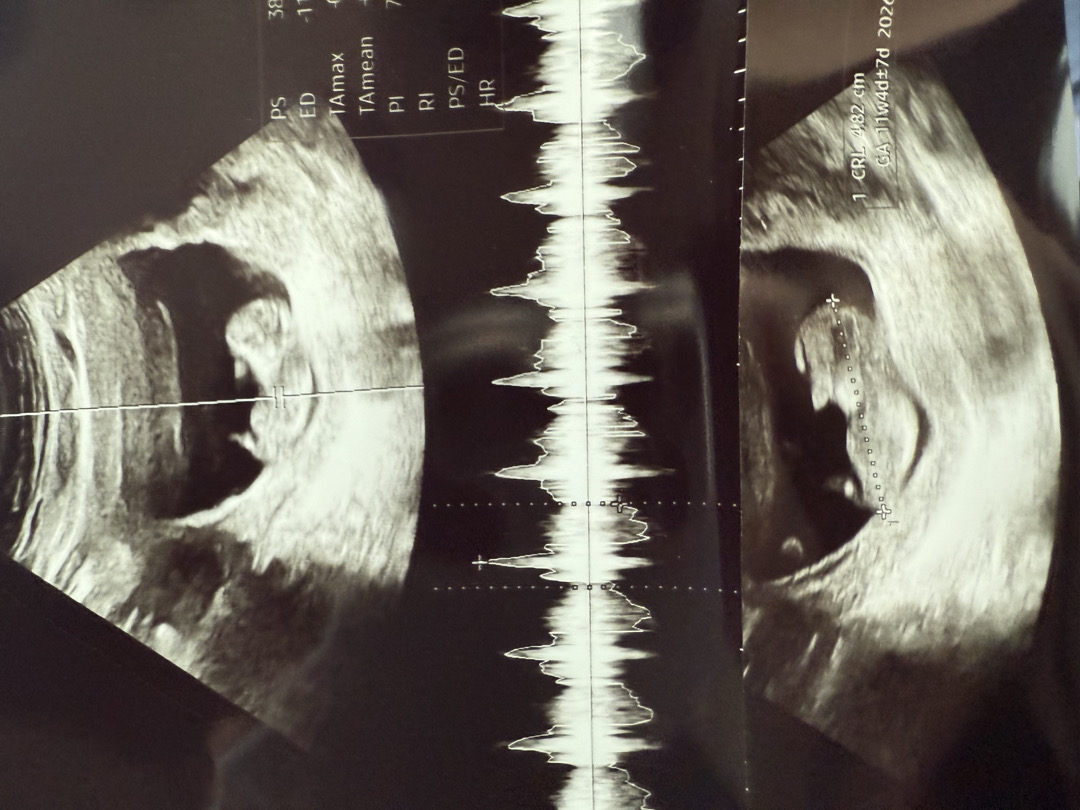

11주차 각도법 궁금해요 한번 봐주세요!!!

현재 시기에 각도법으로 알수있다던데 여러분이 보시기엔 딸인가요 아들인가요??🥹

12주차는 돼야 돼요